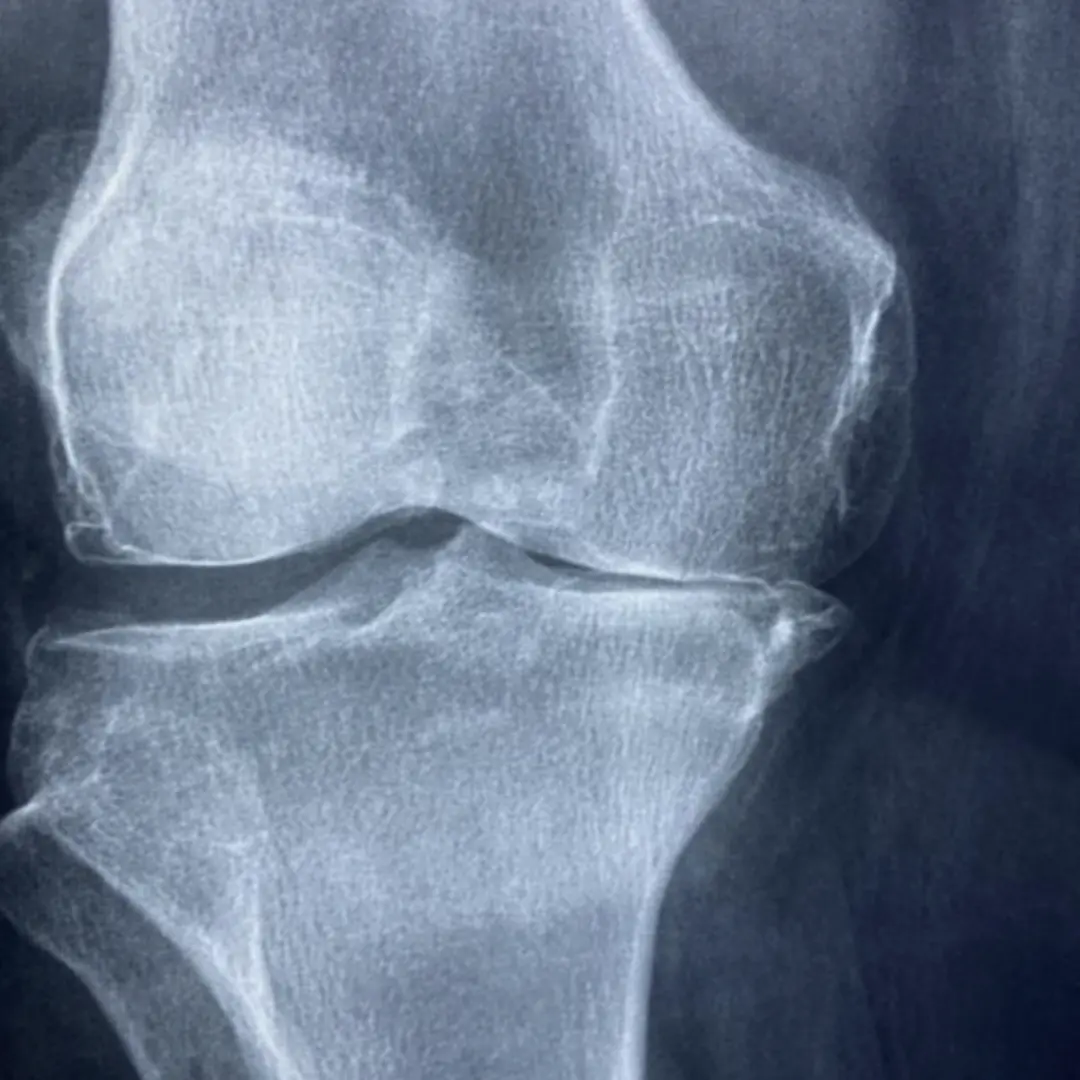

- 퇴행성 관절염으로 고통받는 분:

- 가장 직접적인 도움을 받을 수 있는 대상입니다. 연골이 닳아 통증과 염증을 느끼는 분들에게 콘드로이친은 연골 구성 성분을 보충하고 염증을 완화하여 통증 감소와 관절 기능 개선에 기여할 수 있습니다.